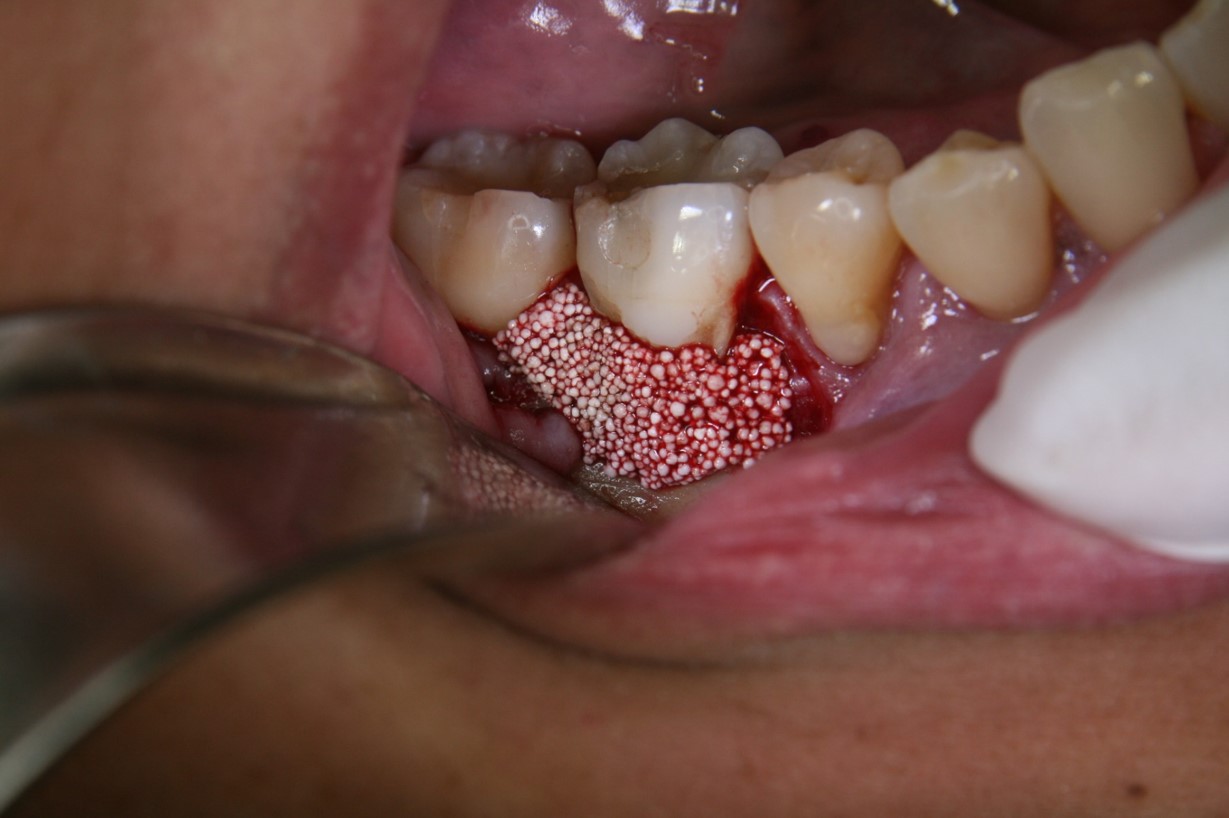

Fig 5. Patient presented with a periodontal defect.

Figure 5

Fig 6. A flap was required to expose and clean the defect area (ie, exposed root, furcation) using ethylenediaminetetraacetic acid (EDTA).

Figure 6

Fig 7. PLGA alloplast bone grafting material was placed and molded into shape and, once the bone material solidifies, a membrane would be placed and the area closed with the soft tissue.

Figure 7